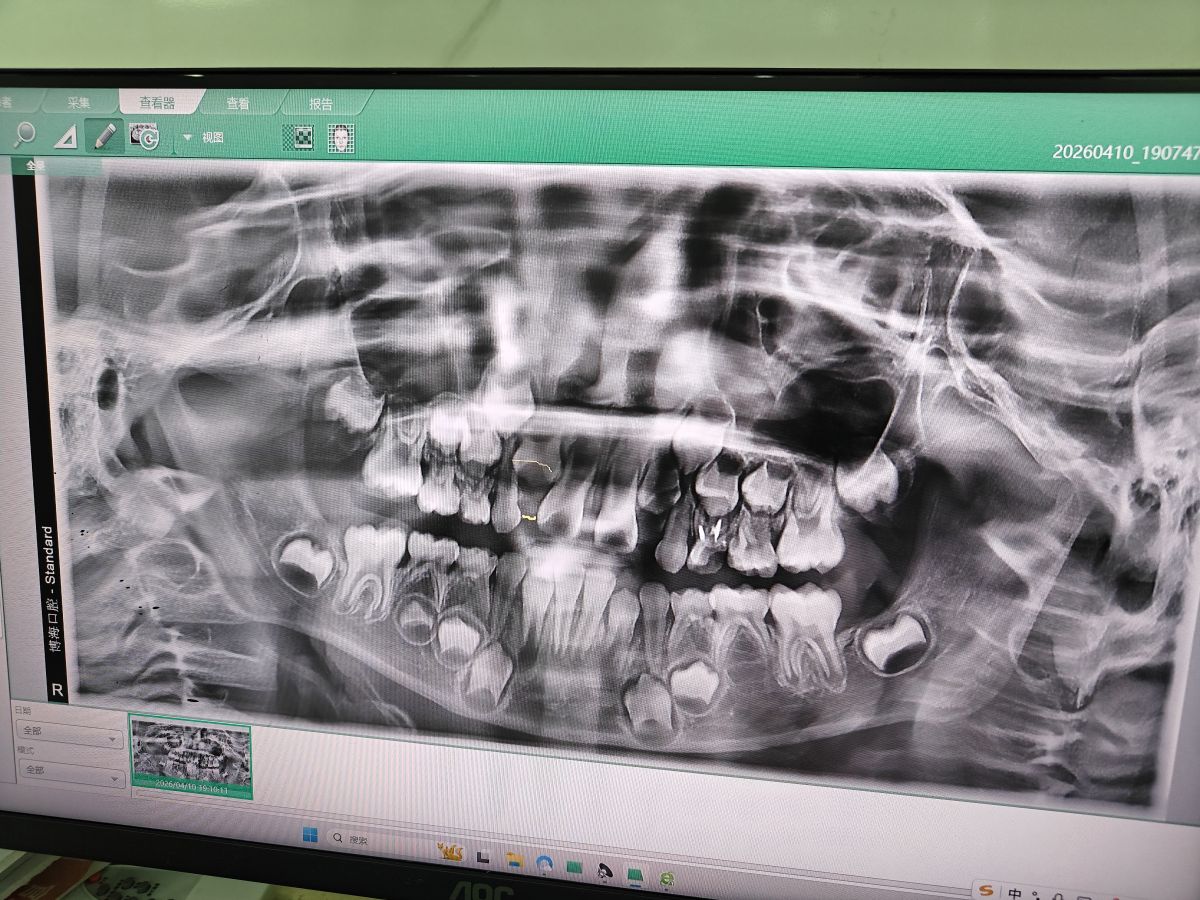

又去看牙医🦷

2026年04月10日